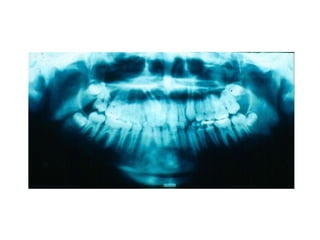

TRANSPOSIÇÃO TOTAL - CANINO COM INCISIVO LATERAL MANOBRAS PARA CORREÇÃO DA ROTA DE ERUPÇÃO